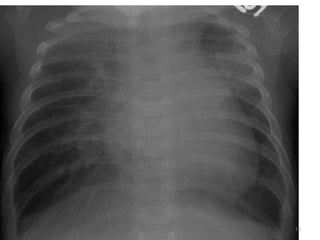

- CXR - Cardiomegaly

- Narrow mediastinum

- Increased pulmonary blood flow